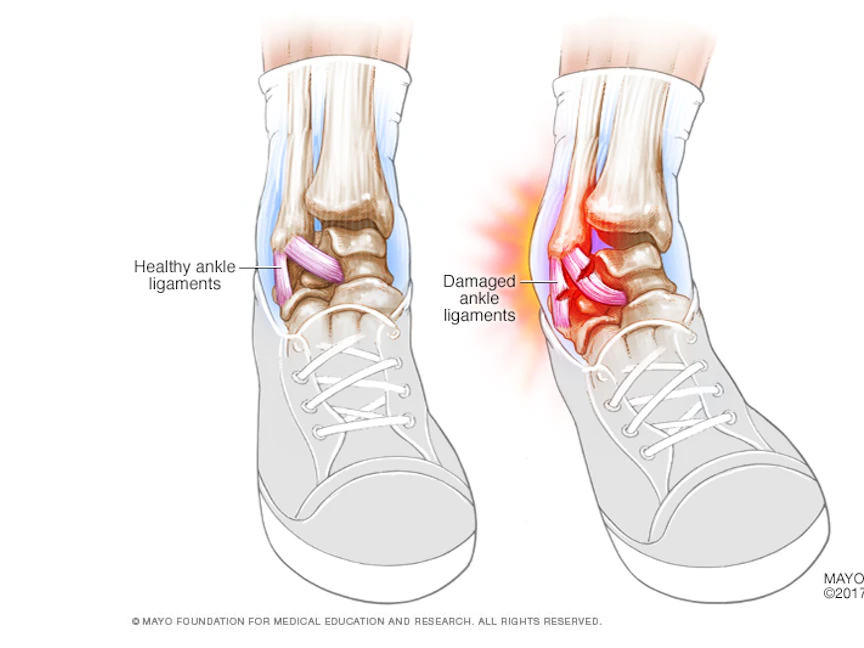

ما هو التواء المفاصل؟، التواء المفصل هو شدّ أو تمزّق في الأربطة التي تتكون من أشرطة نسيجية ليفية قوية تربط عظمتين مع بعضهما داخل المفصل، ويُعَدُّ الكاحل أكثر موضع عرضة للالتواء.

- الكاحل

من خلال المشي أو التمرين على سطح غير مستوٍ، والهبوط بشكل غريب من القفز.